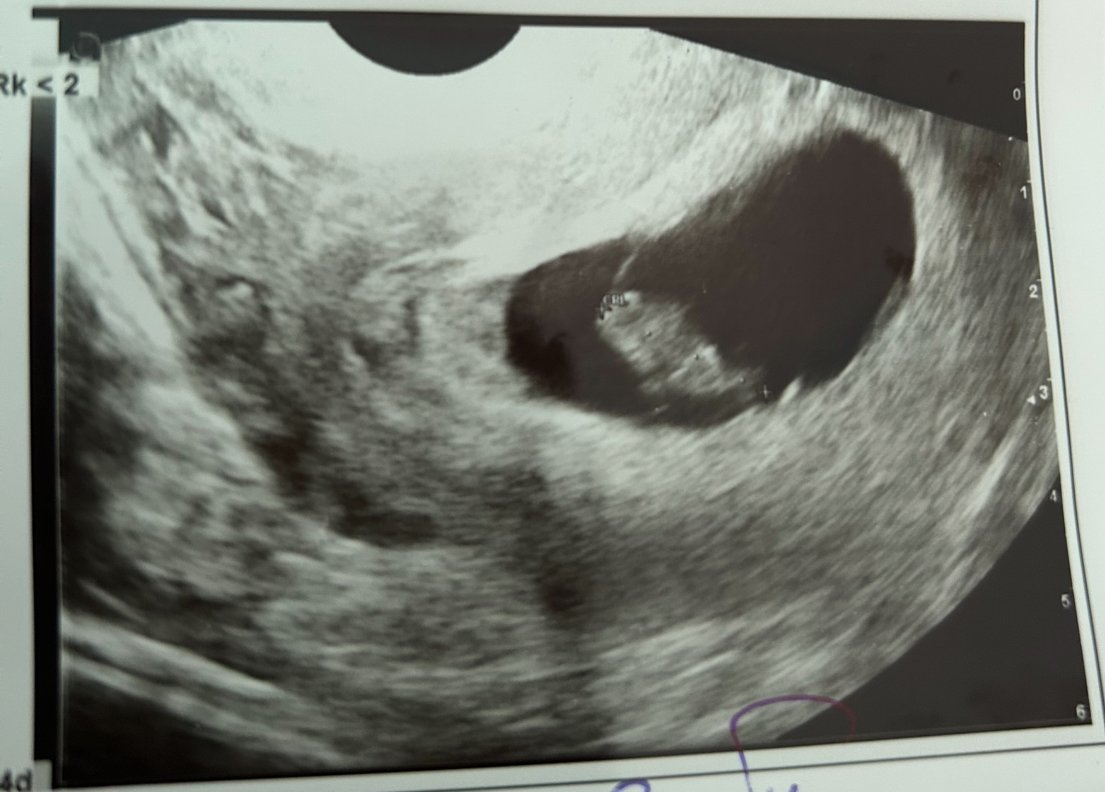

Здравейте, доктора каза, че ембриона отговаря за 8 г с . Но няма сърдечна дейност, можели по късно да се чуе!

Melaniiiiiiii,съжалявам,но ако сега няма пулс едва ли по-късно би се чул.